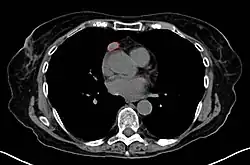

When a thymoma is suspected, a CT/CAT scan is generally performed to estimate the size and extent of the tumor, and the lesion is sampled with a CT-guided needle biopsy. Increased vascular enhancement on CT scans can be indicative of malignancy, as can be pleural deposits.[2] Limited biopsies are associated with a very small risk of pneumomediastinum or mediastinitis and an even-lower risk of damaging the heart or large blood vessels. Sometimes thymoma metastasize for instance to the abdomen.[6]

The diagnosis is made via histologic examination by a pathologist, after obtaining a tissue sample of the mass. Final tumor classification and staging is accomplished pathologically after formal surgical removal of the thymic tumor.